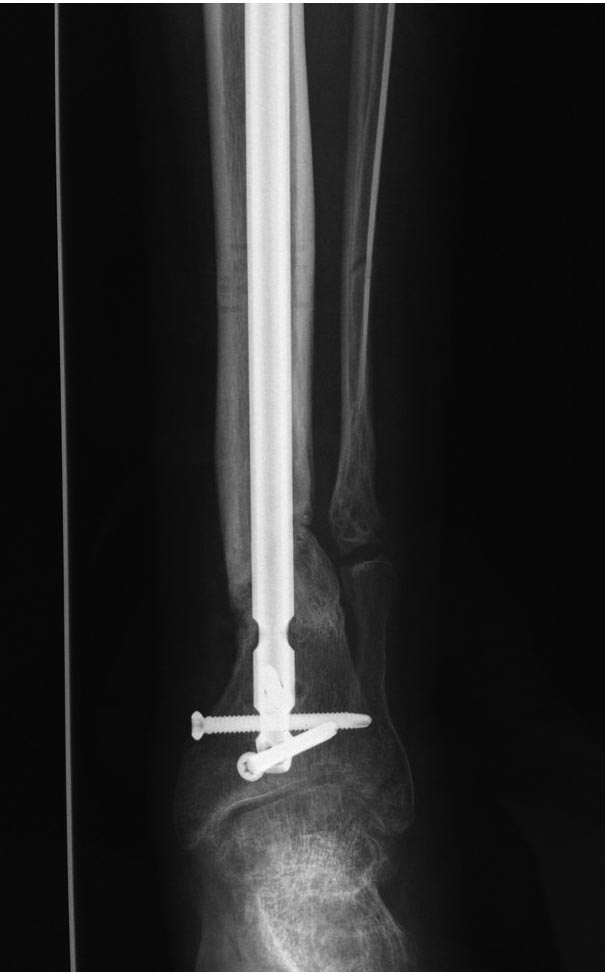

Вариант 1- выполнить реостеосинтез с рассверливанием КМК и на 12 мм

диаметра гвоздь (стоит 11 мм)и убрать ротацию стопы руками одномоментно

или одномоментно при помощи АНФ во время операции.

Вариант 2 выполнить удаление гвоздя, сделать все то же, что 6 месяцев

назад, но с восстановлением анатомических взаимоотношений в

голеностопном суставе.

Вариант 3 Двухэтапно, вторым этапом пластина на большеберцовую кость +

костная пластика области несращения.

Вариант 4 удаление гвоздя и лечение в КДА.

Вопросы: 1. Какой вариант оперативного лечения будет оптимальным в

данном случае. 2. При двухэтапной методике в дистальном отломке имеется

канал от гвоздя, как направить гвоздь к наружному отделу дистального

отломка большеберцовой кости. Есть опасения, что гвоздик может пойти по

тому же каналу. Использовать поллер спицы или винты - сработают ли? И

достаточна ли будет жесткость фиксации дистального отломка

большеберцовой кости на гвоздике при 3 4 винтах при реостеосинтезе гвоздем.

3. Нужен ли остеосинтез малоберцовой кости в нижней трети, с целью

создания латеральной опоры. К сообществу за советом.